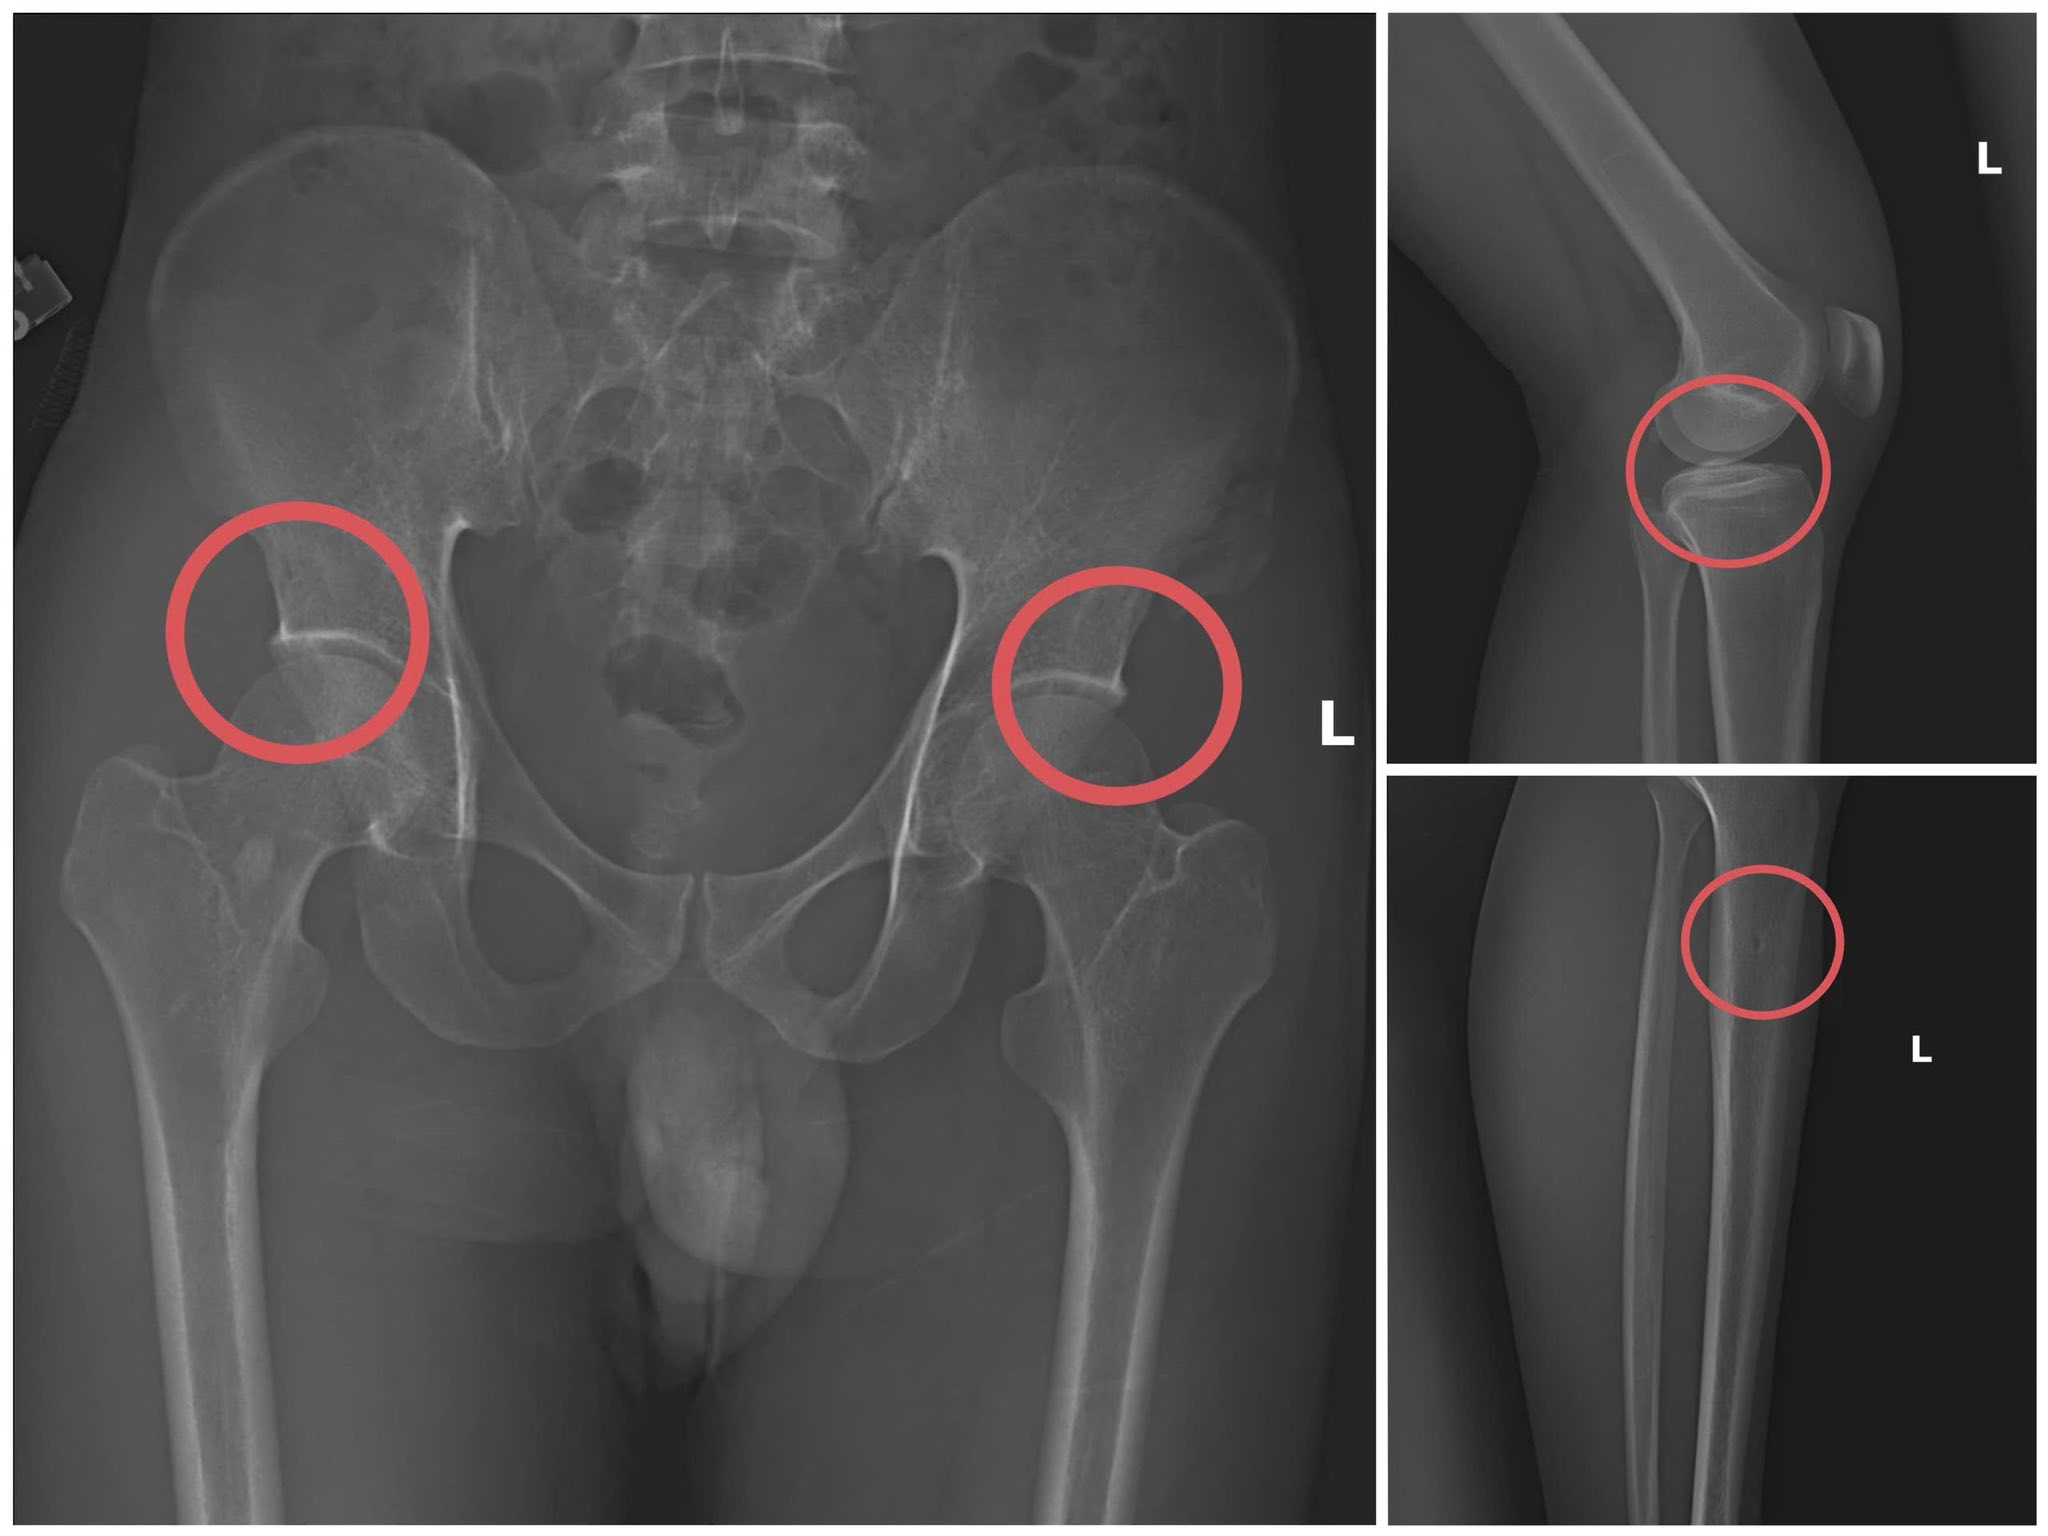

Thông qua các tài liệu thu thập được, Cơ quan Cảnh sát điều tra làm rõ đối tượng Tạ Minh Châu, SN 1995, nguyên cán bộ Trung tâm Y tế huyện Cẩm Khê, là kẻ chủ mưu, cầm đầu. Lợi dụng thời gian dài công tác trong ngành y và am hiểu sâu cấu tạo xương – khớp, cũng như cơ chế chi trả bảo hiểm đối với các thương tích gãy xương giá trị cao, Châu đã dựng lên một quy trình trục lợi bài bản, từ việc vận động mua bảo hiểm, tổ chức gây thương tích, đến hợp thức hóa hồ sơ bệnh án để chiếm đoạt tiền của các công ty bảo hiểm.